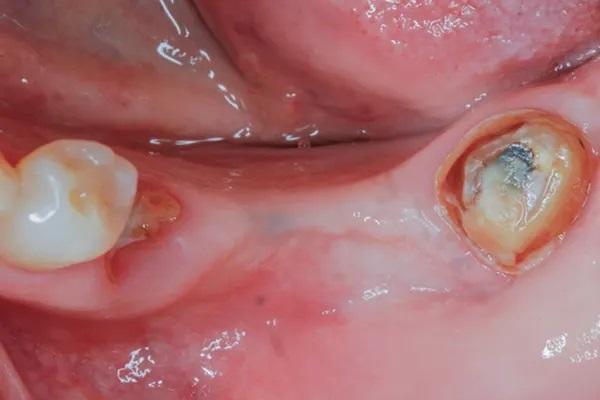

Реципиентный участок был подготовлен, как описано ранее, и за апикальным пределом дефекта установили один апикальный фиксирующий винт (Фото 14). В этом случае получили комбинацию 50:50 аутогенного и аллогенного композитного трансплантата (OraGRAFT MD 70/30) и адаптировали его к дефекту. Кроме того, для фиксации костного трансплантата в дефекте и обеспечения дополнительной стабильности комплекса трансплантат-мембрана использовали ламинарную пластину (Фото 15). Затем один стабилизирующий шов обернули вокруг апикального фиксирующего винта и закрепили на небном лоскуте таким же образом, как описано выше. Дополнительный фиксирующий винт устанавливали на несколько миллиметров апикальнее к первому, чтобы полностью ограничить дефект. Начальный винт оставили, так как он обеспечивал некоторую начальную стабильность ламинарной пластины, помогая предотвратить ее случайное перемещение в апикальном направлении. Первичное ушивание выполняли по тому же протоколу, что был описан выше, и пациента выписали домой на реабилитацию.

Фото 14: Винт для фиксации мембраны, закрепленный на апикальном участке дефекта, и отверстия в костный мозг на буккальной стороне альвеолярного гребня.

Фото 15: Ламинарная пластина, закрепленная над трансплантатом с помощью одного стабилизирующего шва, обернутого вокруг апикального фиксирующего винта и закрепленного на небном лоскуте; обратите внимание на дополнительный винт, обеспечивающий начальную стабильность ламинарной пластины.